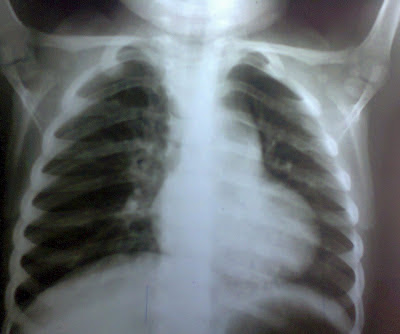

La Rx PA de tórax es la siguiente: